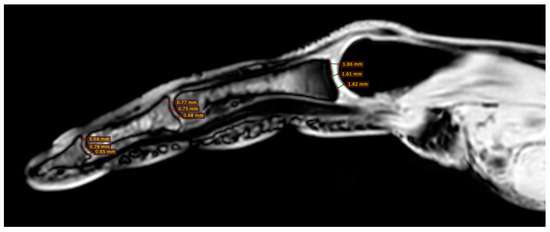

2.4. Magnetic Resonance Imaging

Cartilage Thickness and Distal Phalanx Length in MRI